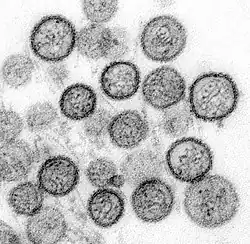

Individual hantavirus particles (virions) are usually spherical, but may be oval, pleomorphic,[13] or tubular.[4] The diameter of the virion is 70–350 nanometers (nm).[10] The lipid envelope is about 5 nm thick. Embedded in the envelope are the surface spike glycoproteins Gn and Gc,[2] which are arranged in a lattice pattern.[10] Each surface spike is composed of a tetramer of Gn and Gc (four units each) that has four-fold rotational symmetry and extends about 10 nm out from the envelope.[10] Gn forms the stalk of the spike and Gc the head.[4] Inside the envelope are helical nucleocapsids made of many copies of the nucleocapsid protein N, which interact with the virus's genome and RdRp.[2] Hantaviruses do not encode matrix proteins to assist with structuring the virion, so how surface proteins organize into a sphere with a symmetrical lattice is not yet known.[14]